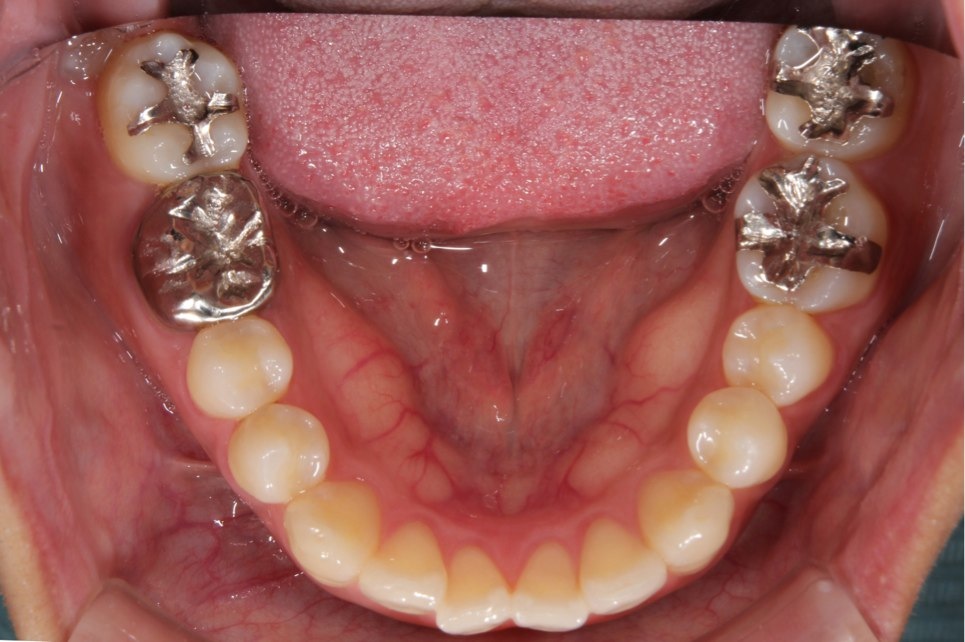

左右のダイレクトボンディング

費用5万円×4本

リスクとして欠ける可能性がある(修復可能)。